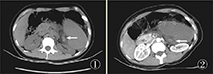

患者女,27岁。因上腹部疼痛1 d入院,疼痛呈持续性刺痛无放散。无恶心、呕吐,无发热、黄染,无腹泻及里急后重。无尿频、尿急、尿痛。查体:腹式呼吸减弱,上腹压痛,以左上腹为主,伴反跳痛,轻度肌紧张。Murrphy征阴性。肝胆肋下未触及,脾肋下可触及。脾区叩痛明显。血常规:WBC:14.28×109/L,RBC:3.76×1012/L,HGB:87 g/L。凝血常规:PT-sec:11.5 s,PT-INR:0.84,PT:111.00%,FIB:4.59 g/L,TT:14.7 s。尿常规无异常、肝功未见异常。心电、胸片未见异常。肿瘤标志物:CEA:0.71 ng/ml,CA-199 153.35 U/ml。腹部CT示:脾脏增大,大小约11.6 cm×6.1 cm,CT值40 HU,腹腔内肠管、左肾及胰腺受压移位、变形。增强扫描后,动脉期、延迟期,脾脏实质均未见明显强化,CT值约42 HU;脾动脉于脾门后未见显影,脾动脉未见明显增粗、扩张,脾静脉未见造影剂充盈,脾静脉走形呈螺旋状改变,脾周围见少量积液(图1)。诊断:脾大、脾实质未见强化,脾动脉于脾门后闭塞,脾静脉扭曲。急诊在全麻下行剖腹探查、脾切除术,术中见脾脏被大网膜包裹,与周围组织粘连,分离粘连后见脾脏明显增大,约12 cm×8 cm×4 cm,呈暗红色,包膜明显增厚,脾实质质地硬,包膜与脾实质分离,脾周围少量暗红血性液体。脾门处见脾动静脉迂曲、增粗,内可见血栓充满(图2),未见扭转。术后患者恢复顺利。术后病理:脾脏18 cm×10 cm×4 cm,切面实性、暗红色,脾动、静脉见凝血,血管内可见血栓。术后10 d痊愈出院,术后随访7个月,患者状态良好,无不适,血小板已经降至正常,未再出现腹部疼痛。